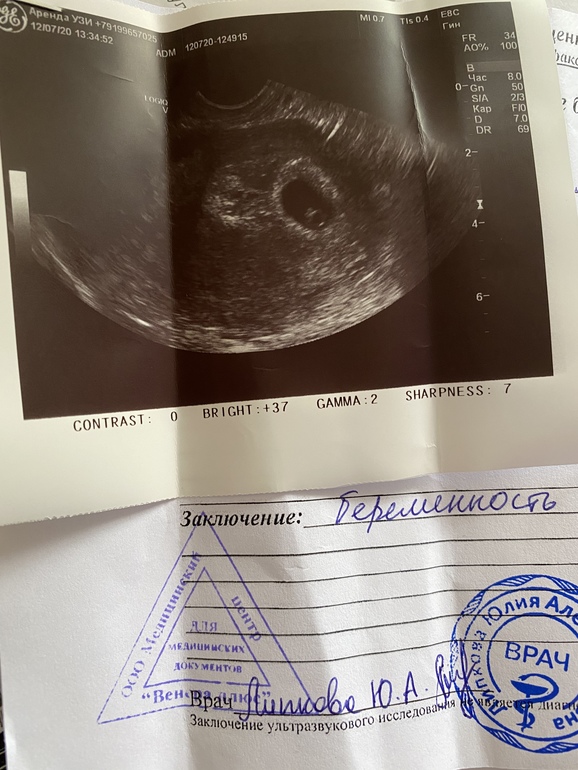

Узи 🥰

Сходила на узи)Пока успокоилась)

Чувствую себя по разному,по утрам всё бесит и тошнит..отвернуло от яиц и помидор и рыбы не ем их.Хочется фруктов,поспать и поплакать)Описание какое то короткое..не написала ктр(но врач сказала что всё хорошо и это главное!Показывала как бьётся сердечко на мониторе незабываемое чувство 🥰

Ну вот узистка какая то молодая была ни ктр не написала ни чсс...

Ну эмбрион я видела она мне его показывала и показывала как сердечко бал бьётся чёрная точка пульсировала на экране🥰

Вот моё узи с младшим сыном примерно на этом же сроке

По Рамзи смотрят на сроке 6-7 недель про прикреплению эмбриона,если УЗИ трансвагинально,то слева мальчик,а справа девочка,если по животу,то наооброт слева девочка,а справа - мальчик,вот для примера мое узи на сроке 6+2 УЗИ трансвагинально и у меня прикрепление слева,по нему у меня мальчик,но так и есть

А вот у меня где то посередине?)

Ну да почти по середине,но чуть левее мне кажется

Отличные новости🥰. По методу Рамзи девчуоя, если УЗИ было вагинаььное

Да узи вагинальное)спасибо😍очень надеюсь что это правда 🥰

Смотрят пол по прикрепления малыша

Ну видно малыша в по одном пузыре и он справа и плацента больше справа